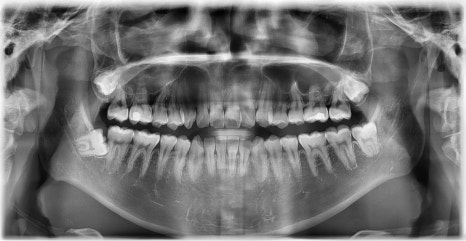

2024.12. 초진 파노라마 엑스레이 - 연세정원치과

외관상으로는 아랫입술이 돌출되어 보이고 아래 치아가 좌측으로 치우치면서 치아 중심선(midline)이 맞지 않는 상태였습니다. 또한 환자는 어릴 적 넘어지면서 앞니가 깨졌던 외상 병력이 있었고, 그 영향으로 앞니 뿌리가 부분적으로 흡수된 상태였습니다.

정밀 검진 결과, 하악 치열이 좌측으로 틀어져 있었고 그로 인해 위아래 치아 중심선이 일치하지 않았습니다. 아래 치열이 전체적으로 전방 위치하여 아래 입술 돌출이 더 도드라져 보이는 상태였습니다. 그리고 상악궁이 하악궁보다 좁아서 앞니 부위 일부 반대로 물리는 치아 교합도 관찰되었습니다. 특히 외상 치아의 경우, 교정력 적용시 추가적인 염증성 치근 흡수 위험이 존재하기 때문에, 치료 중 지속적인 관찰이 필수적인 상황이었습니다.